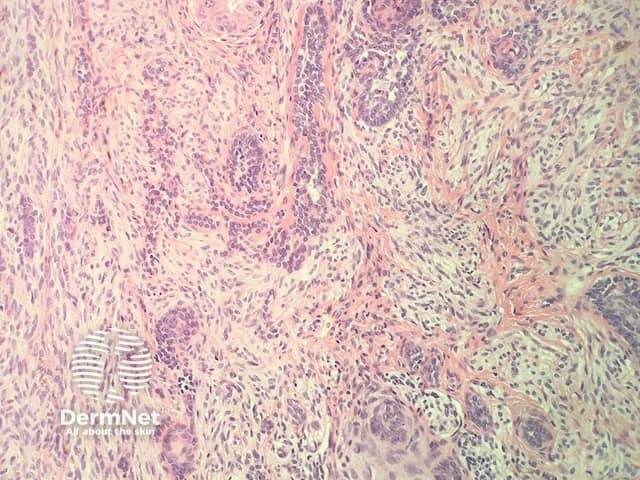

In combined trichoepithelioma and cellular blue naevus, the histopathology shows a fairly well-circumscribed biphasic dermal proliferation involving the full thickness of the dermis and shows tongues of rounded tumour fronts (figure 1). The tumour is composed of intimately mixed populations of melanocytes and basaloid cells. The basaloid cells anastomose in a lace-like pattern and form horn cysts focally (figure 2,3). The follicular component is surrounded by a prominent stroma, which is condensed around the basaloid islands as hair papilla-like structures. The melanocytic component consists of islands of plump spindled cells with abundant pale cytoplasm and minimal pigment and rarer slender dendritic melanocytes with heavy melanin pigmentation (figure 4).

Figure 1